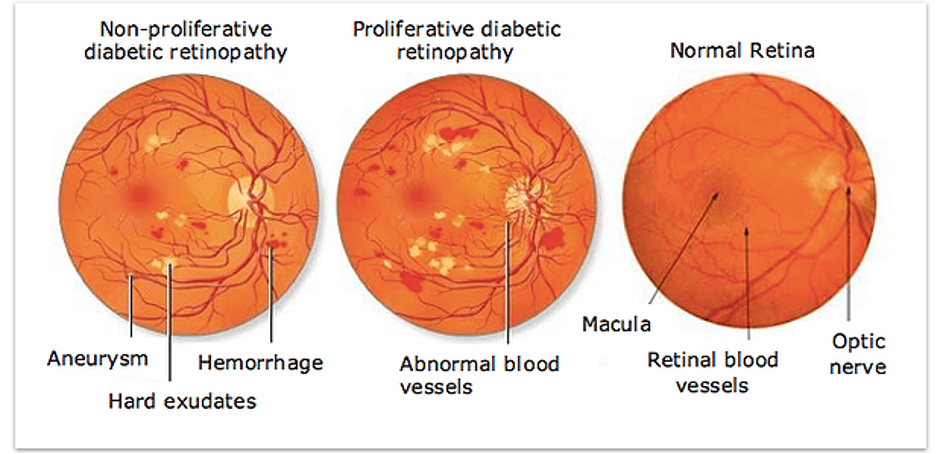

What are the stages of Diabetic Retinopathy?

There are two main stages of diabetic retinopathy.

1. NPDR (non-proliferative diabetic retinopathy)

This is the early stage of diabetic retinopathy.

Leakage in the retina causing: blot and dot bleeding and leakage of fat. Vision may still be very good at this stage.

2. PDR (Proliferative Diabetic Retinopathy)

PDR is the more advanced stage of diabetic retinopathy.

- The retina starts growing new blood vessels: a process called neovascularisation

- These fragile new vessels often bleed within the eye called: vitreous haemorrhage

- These new blood vessels can form fibrous scar tissue.

- Scar tissue can pull on the retina and cause detachment of the retina called: tractional retinal detachment.

Tractional Retinal Detachment

Abnormal blood vessels

Abnormal bleeding in eye